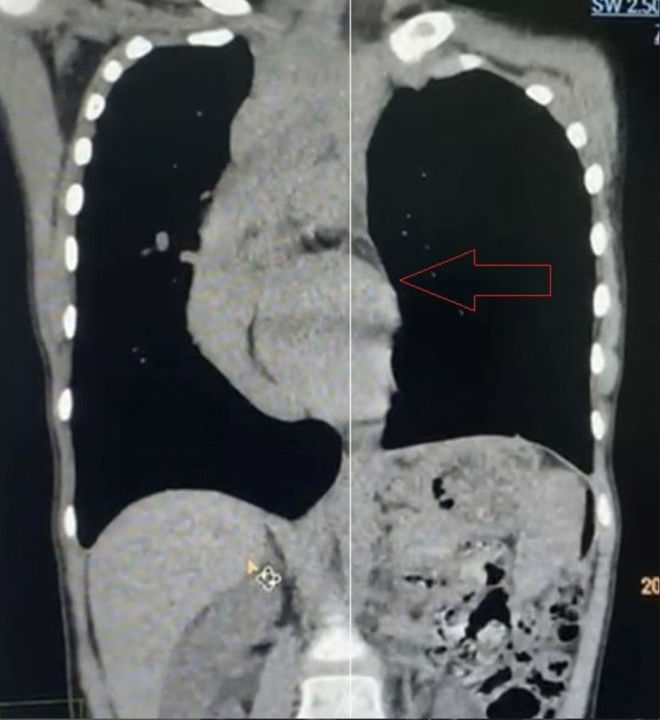

Preoperative Examination

The anterior chest wall shows a severe asymmetric depression, causing marked compression of the heart, which is displaced toward the right thoracic cavity. The patient also presents with scoliosis. She is diagnosed with malignant pectus excavatum.